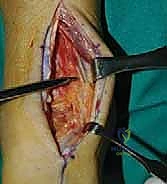

خطوات جراحة تثبيت مفصل الكاحل الأمامي بالتفصيل (Step-by-Step Surgical Procedure)

1. الوضعية والشق الجراحي (Positioning and Incision)

يستلقي المريض على ظهره (Supine position). يتم استخدام عاصبة (Tourniquet) حول الفخذ لتقليل النزيف وتوفير رؤية واضحة. يقوم الدكتور هطيف بإجراء شق طولي أمامي فوق مفصل الكاحل، عادة بين وتر العضلة الظنبوبية الأمامية (Tibialis Anterior) ووتر العضلة الباسطة الطويلة لإصبع القدم